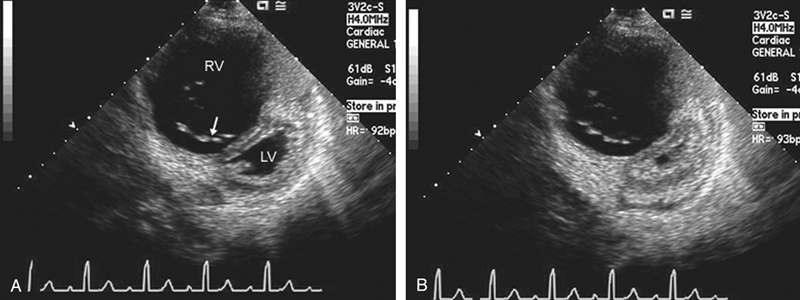

فحوصات تشخيصية لبعض امراض القلب والشرايين التاجية